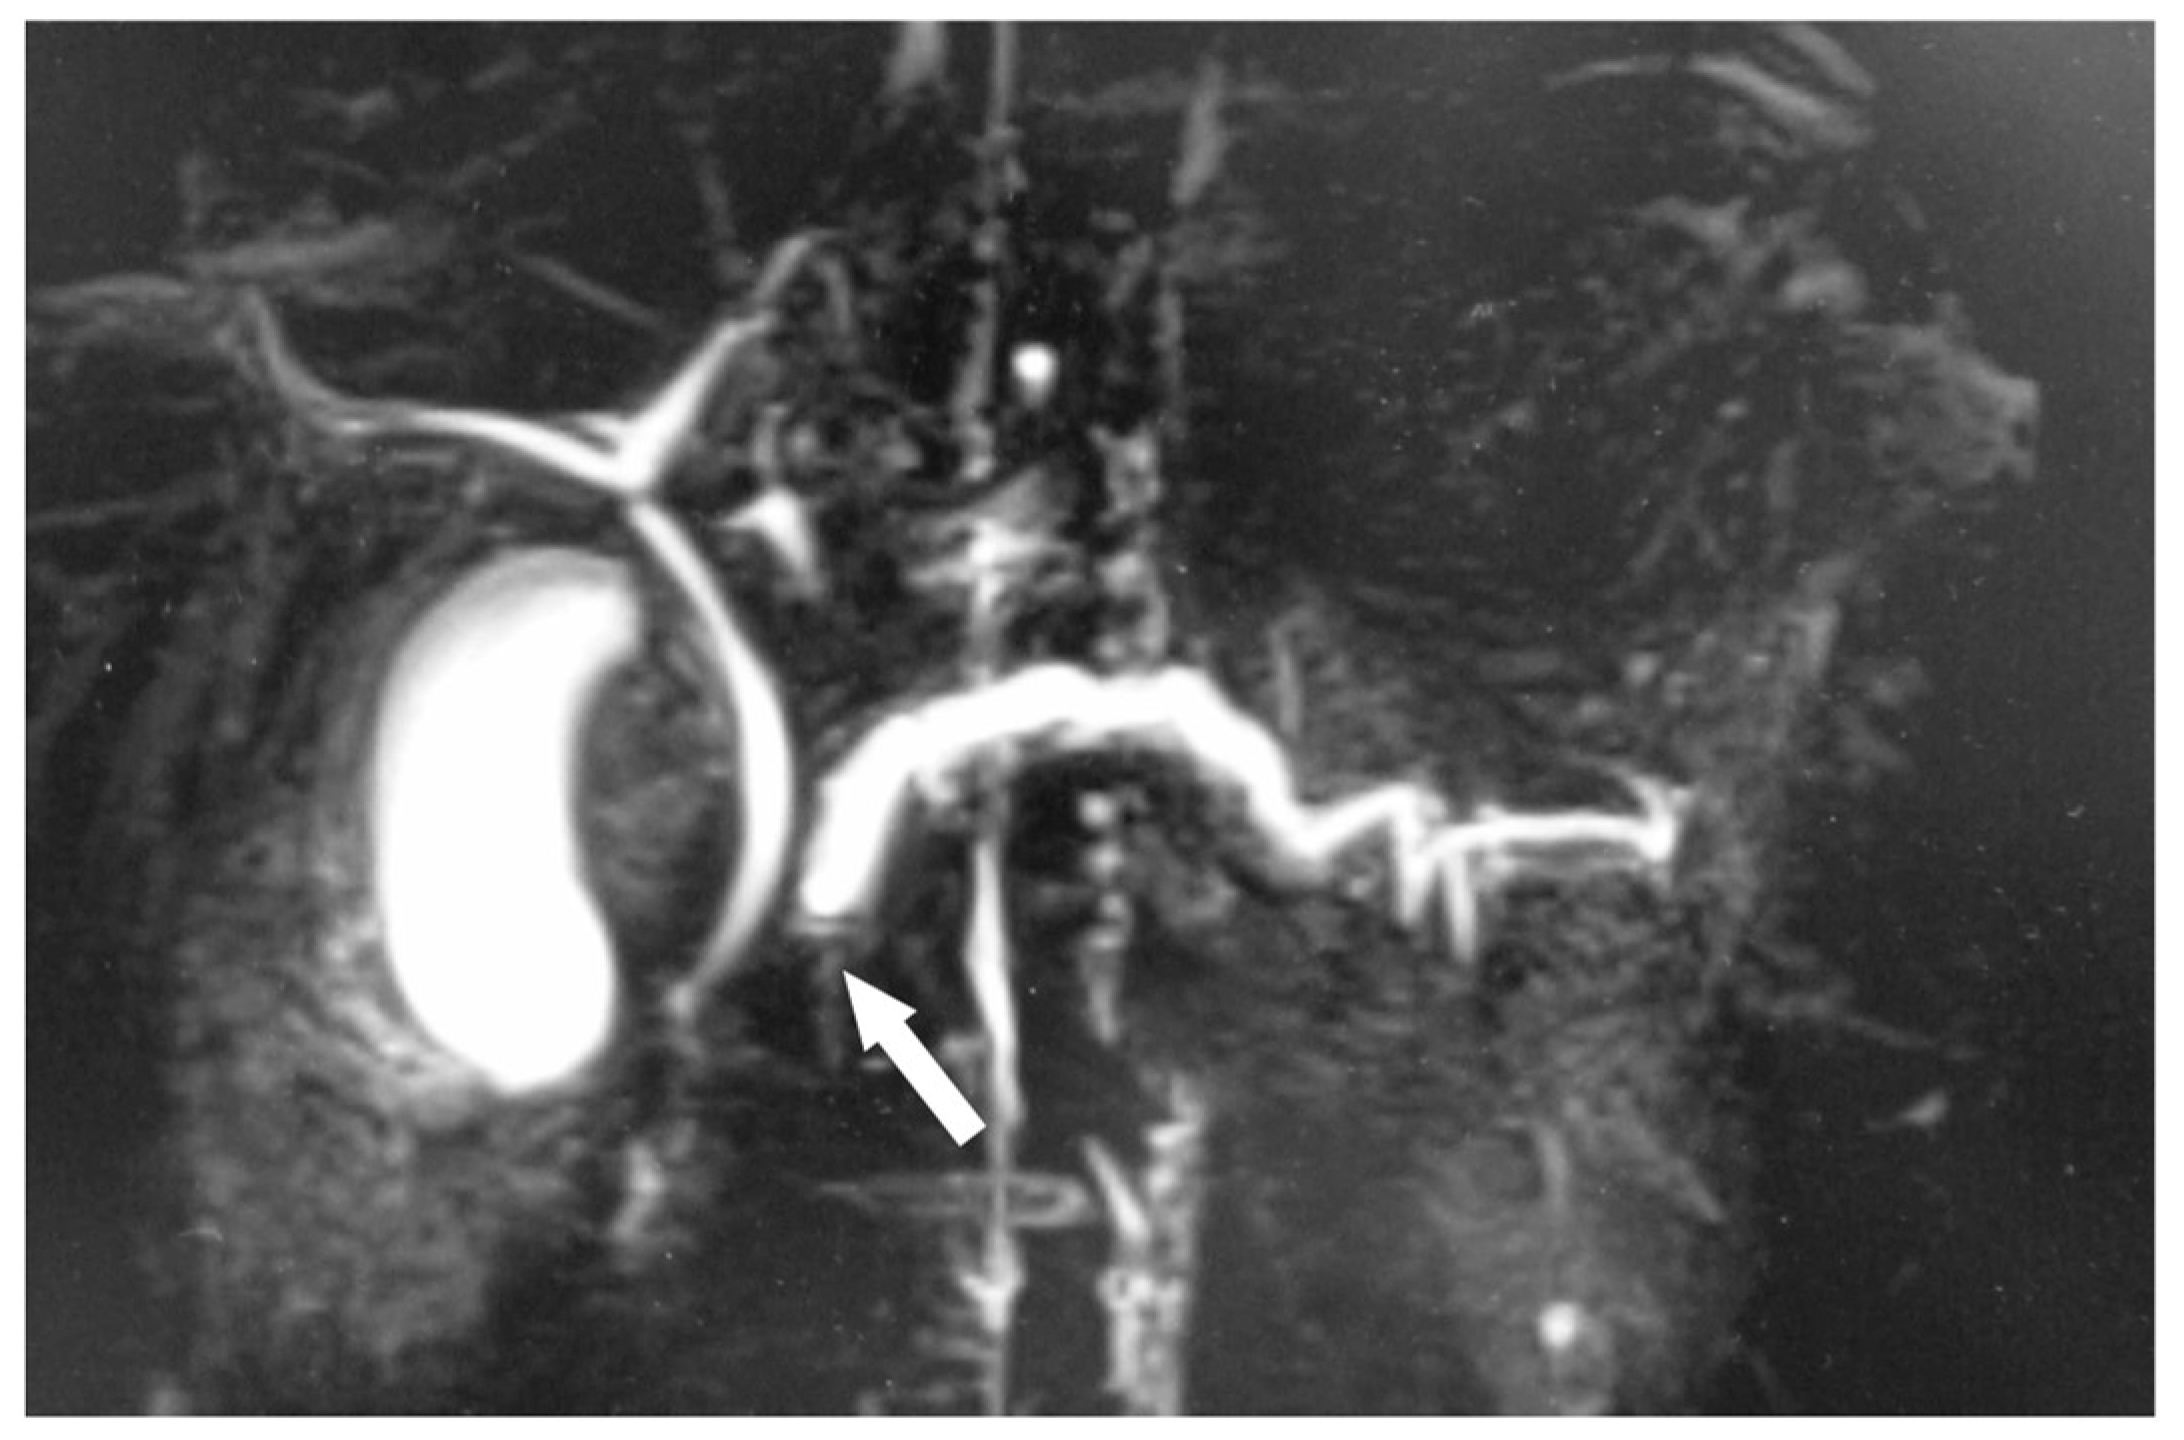

2.2. Clinical Course before Surgery

2.3. Surgical Treatment